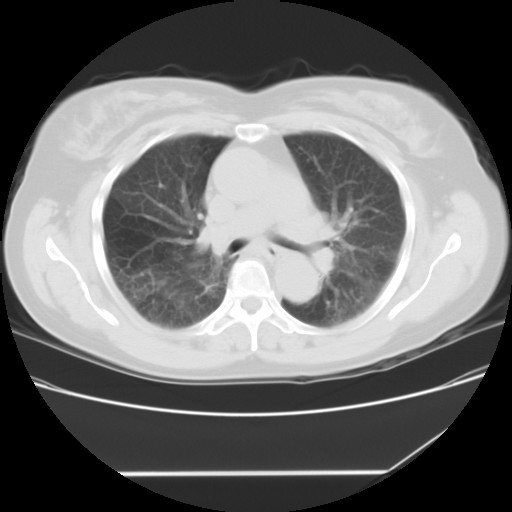

标题: CT24018:女性,62岁,咳嗽4年,无热,胸部CT扫 [打印本页]

女性,62岁,长期咳嗽,既往从事工作有粉尘接触,有高血压病史,110/150mmhg,近日咳嗽加重,脸面浮肿,请大家帮看下,

间质性肺炎,有纤维化趋势。

1)慢性支气管炎并肺部感染、肺气肿。2)肺间质纤维化。